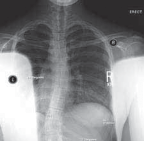

Chapter 63 Hemivertebra Excision Daniel J. Hedequist and John B. Emans DEFINITION A hemivertebra is a congeni…